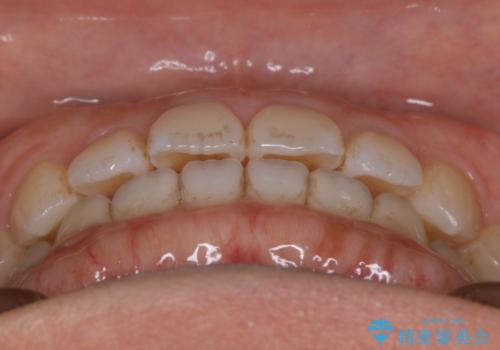

- 矯正治療を主訴にご来院されました。

すきっ歯と噛み合わせの治療をしたいとのことで、インビザラインを用いて矯正治療を行うこととなりました。

すきっ歯の場合、ガタつきを治したりするのに必要なスペースが最初から空いているため、そのスペースを利用して比較的短期間で効率よく治療を進めることが可能となります。

初診時の写真では一見噛み合わせには問題がないように見えても、実際に精密な検査を行うと改善すべき点が見つかる場合も多くあります。

当院では、矯正治療は見た目の改善が主目的ではなく機能面を改善し自然に長持ちする口腔内環境を整えることに重きを置く必要があると考えます。

しかしながら、こちらの理想だけを押し付けるだけが良い治療とは言えないので、患者様と治療のゴールの設定をよく話し合ったうえで方針を決定していくことが最も重要です。